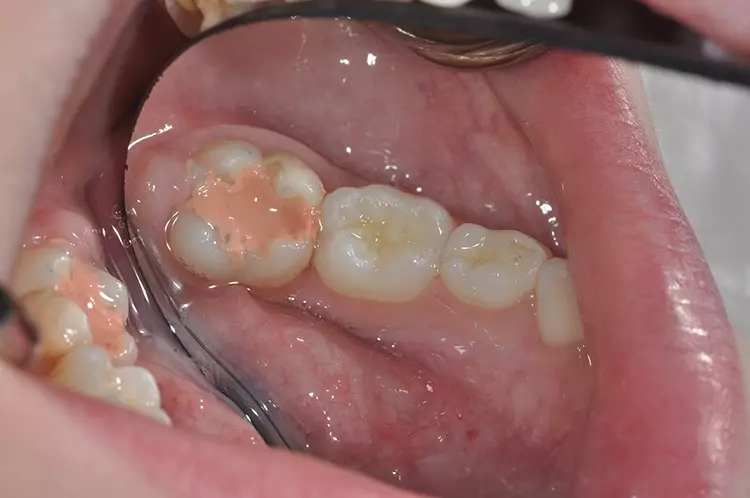

Der Schmelz von MIH-geschädigten Zähnen ist im Vergleich zu gesundem Schmelz durch einen geringeren Mineral- und höheren Proteingehalt gekennzeichnet. Dies zeigt sich anhand eines sehr hohen Anteils an Porositäten (Abb. 3a u. b) und an einer deutlich verringerten Mikrohärte. Die prismatische Struktur des betroffenen Schmelzes wird als weniger dicht beschrieben, mit großen leeren Strukturen und locker gepackten Apatitkristallen.

Diese mikrostrukturellen Anomalien führen zu einer drastischen Verringerung der mechanischen Festigkeit des Schmelzes (d.h. Oberflächenhärte, Verschleißverhalten, Bruchzähigkeit usw.), was natürlich auch zu einem geringen Widerstand gegen die Kaukräfte führt. Darüber hinaus sorgt die inhomogene Oberflächenstruktur, die kein regelmäßiges Muster in der Verteilung des verfügbaren Apatits aufweist, für insgesamt ungünstige Adhäsionsbedingungen [8].

Die strukturellen Besonderheiten reduzieren auch die Verbundfestigkeit zwischen Schmelz und Komposit. Infolgedessen neigen die Füllungsränder im geschädigten Bereich zu Randfrakturen und -spalten und Zahnaussprengungen. Ebenso ist mit Retentionsverlust großer Anteile der Füllung zu rechnen, was in der aktuellen adhäsiven Zahnerhaltungskunde äußerst selten vorkommt [9].